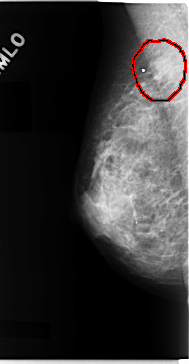

C_0077_1.RIGHT_MLO

LEFT_MLO LINES 4752 PIXELS_PER_LINE 2464 BITS_PER_PIXEL 12 RESOLUTION 50 NON_OVERLAY

FILE: C_0077_1.RIGHT_MLO.OVERLAY

TOTAL_ABNORMALITIES 1

ABNORMALITY 1

LESION_TYPE MASS SHAPE IRREGULAR MARGINS ILL_DEFINED

ASSESSMENT 4

SUBTLETY 3

PATHOLOGY MALIGNANT

TOTAL_OUTLINES 1

BOUNDARY